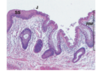

What are the 4 kinds of papillae and their functions?

1) Filiform - for gripping with no tast buds (majority) 2) Fungiform - taste buds 3) Foliate (laterally) 4) Circumvallate (large papillae at the back) - taste buds